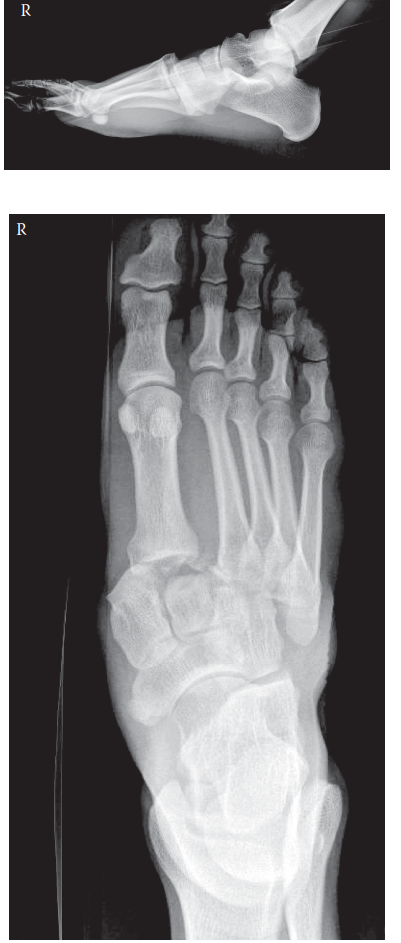

These are radiographs as well as a clinical photograph of the right foot of a 68-year-old man who stumbled do…